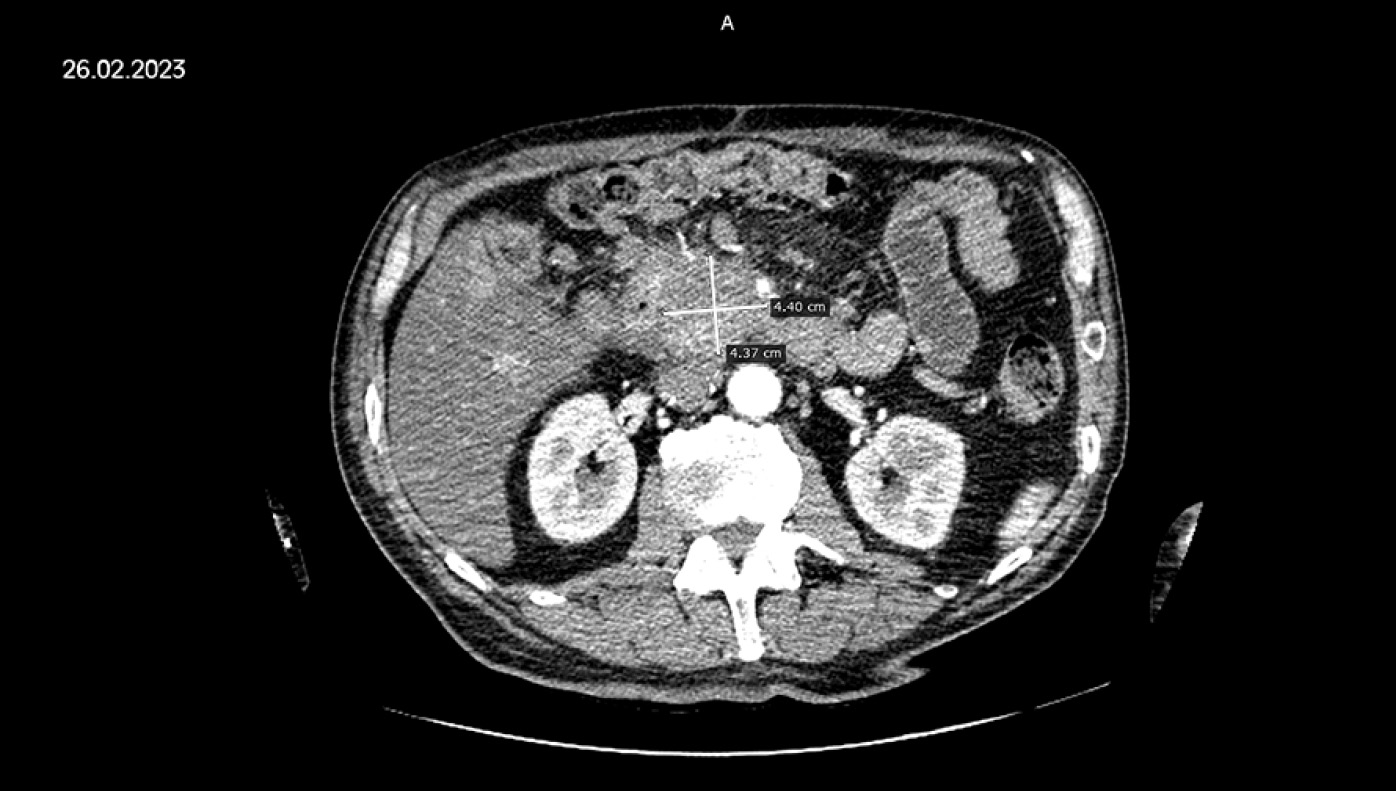

По данным контрольной инструментальной диагностики от 26.02.2023 г., в головке поджелудочной железы сохраняется образование размером 44,0×43,7 мм, прилегающее к петле 12-перстной кишки, воротной вене, чревному стволу (рис. 2). Верхняя брыжеечная артерия резко сужена, полностью в строме образования, верхняя брыжеечная вена не визуализируется (инвазирована).

Рис. 2. Компьютерная томография от 26.02.2023 г. Образование головки поджелудочной железы после трёх курсов цитокиногенетической терапии.

Fig. 2. Computed tomography from 26.02.2023. Formation of the head of the pancreas after three courses of cytokinogenetic therapy.

Сохраняются увеличенные мезентериальные лимфатические узлы (20×8 мм), тогда как ранее выявленные парааортальные (10×12 мм), межаортальные (8×9 мм) и паракавальные (8×10 мм) лимфатические узлы частично регрессировали. При КТ-оценке результата терапии по критериям RECIST 1.1 общий ответ частичный, СНД 70 мм (-34,9% СНД от 03.12.2022 г.).